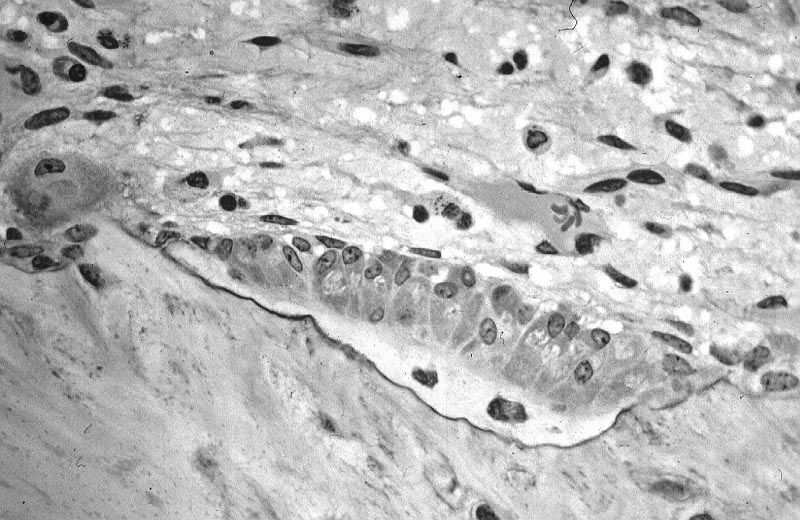

back active osteoblasts

Source: Active osteoblasts

Author: Robert M. Hunt